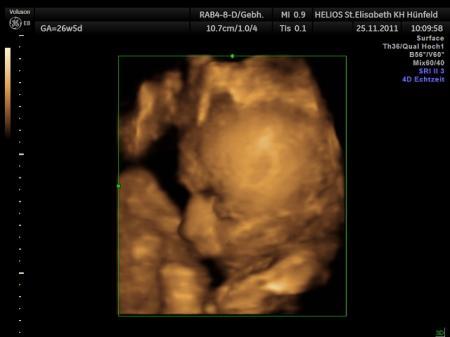

Soo, unsere Maus ist jetzt 41 cm gross(recht zierlich) und wiegt 1700g !!! Sie war gerade fleißig am Daumen lutschen! Wie immer! Glaub wenn sie da ist will sie sofort andocken:-D CTG war unauffällig, keine Wehentätigkeit und Muttermund ist auch noch fest verschlossen! sie liegt schon in der richtigen Position und tritt der Mama immer schön in die Rippen! Bei mir ist auch alles ok, sämtliche Werte, bis auf die wasserablagerungen, ist nen ordentlicher Schub gekommen!